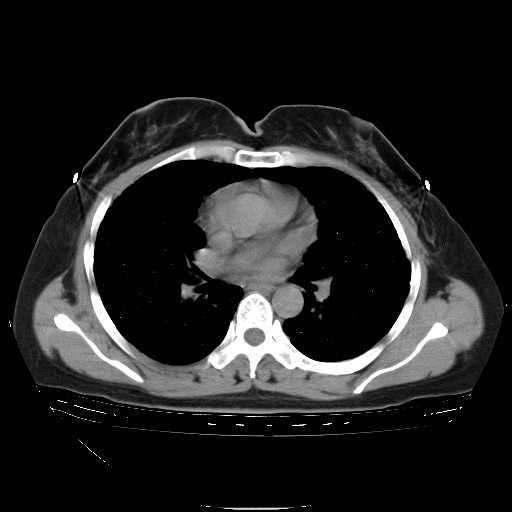

f50,肺ca治疗后,做过穿刺,确诊是肺ca,大家看看这是去年12月做的

考虑  腺癌肺内转移,治疗较前病灶缩小、减少

肺癌并肺内转移,这种疾病治疗后在影像上看略有好转,不是很显著,但是肿瘤治疗效果影像只是一方面。

支持肺癌并肺内淋巴管炎,  原发灶小了,但转移较前片明显了.

标准的细支气管肺泡癌呀!治疗后病情有所控制,也没治愈的迹象!